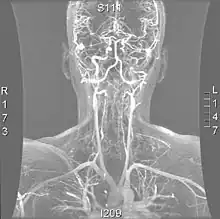

Cerebral Angiogram obtained using an iodine based contrast medium | |

Cerebral atherosclerosis is a type of atherosclerosis where build-up of plaque in the blood vessels of the brain occurs. Some of the main components of the plaques are connective tissue, extracellular matrix, including collagen, proteoglycans, fibronectin, and elastic fibers; crystalline cholesterol, cholesteryl esters, and phospholipids; cells such as monocyte derived macrophages, T-lymphocytes, and smooth muscle cells.[1] The plaque that builds up can lead to further complications such as stroke, as the plaque disrupts blood flow within the intracranial arterioles. This causes the downstream sections of the brain that would normally be supplied by the blocked artery to suffer from ischemia.[2] Diagnosis of the disease is normally done through imaging technology such as angiograms or magnetic resonance imaging. The risk of cerebral atherosclerosis and its associated diseases appears to increase with increasing age;[3] however there are numerous factors that can be controlled in attempt to lessen risk.[4]

Due to positive remodeling the plaque build-up shown on angiogram may appear further downstream on the x-ray where the luminal diameter would look normal even though there is severe narrowing at the real site. Because angiograms require x-rays to be visualized the number of times an individual can have it done over a year is limited by the guidelines for the amount of radiation they can be exposed to in a one-year period.[2]

Magnetic resonance imaging has the ability to quantify the plaque anatomy and composition. This allows physicians to determine certain characteristics of the plaque such as how likely it is to break away from the wall and become an embolus. MRI does not use ionizing radiation, so the number of times that it is used on a single person is not a concern; however since it uses strong magnetic fields those who have metal implants cannot use this technique.[1][2]